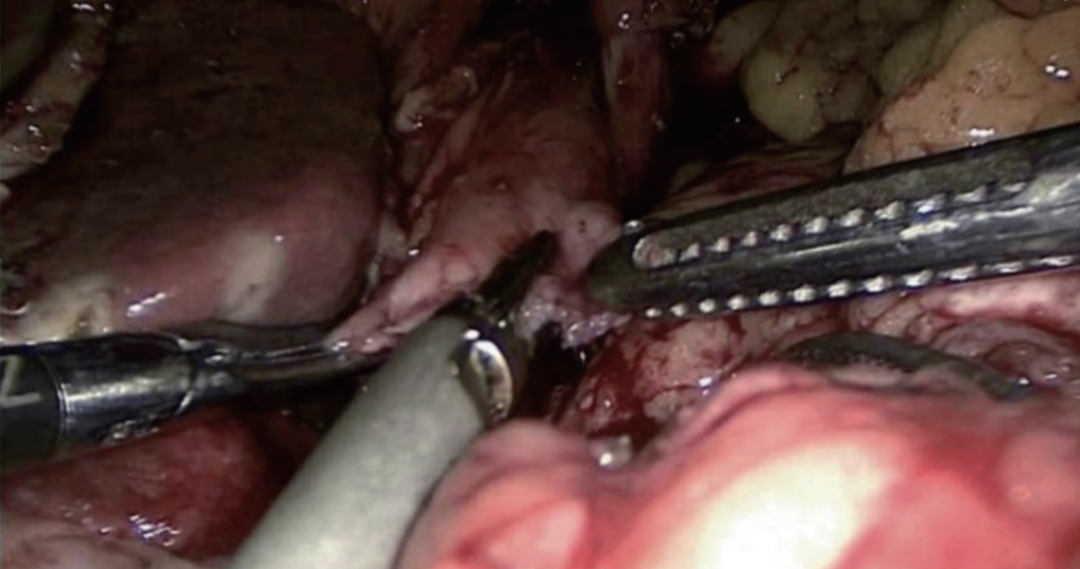

切开食管断端右侧角约5 mm,该切口应该与断端平行,即与食管纵行肌垂直,以防吻合时食管撕裂,经该口将胃管穿出(图8~图9)。用60 mm直线切割吻合器钉仓臂自远端向近端插入远端空肠盲端,抵钉臂在胃管引导下插入食管,行食管-空肠重叠顺蠕动侧侧吻合(Overlap吻合)(图10~图11)。吻合时建议将空肠盲端塞入下纵隔中,以避免膈肌卡压吻合口上端,造成吻合口并发症(图12~图13)。用倒刺线关闭共同开口(共同开口关闭方向应与肠管长轴方向垂直),先全层连续缝合,后浆肌层连续缝合包埋(图14~图15)。将吻合处空肠缝合固定于左侧膈肌脚,防止空肠盲端滑出下纵隔;并固定Y袢于肝胃韧带、十二指肠,防止术后空肠活动度过大导致扭转(图16~图19)。完成食管-空肠重叠顺蠕动侧侧吻合(Overlap吻合)。

图10 在胃管引导下插入吻合器抵钉臂(一)

图11 在胃管引导下插入吻合器抵钉臂(二)